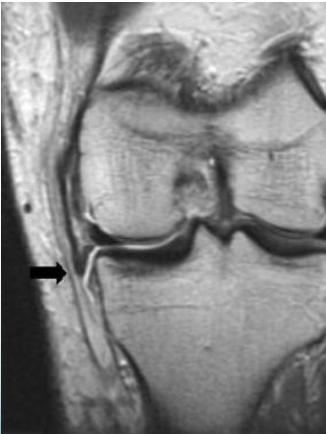

MRI

- Best for assessing soft tissue damage